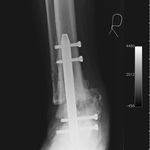

He opted to have a right hind foot arthrodesis, which was carried out utilizing an intramedullary arthrodesis nail, which was performed in July 2011.

He has gone onto have good healing and fusion of the ankle with preservation of his foot and has allowed him to mobilize independently without pain and return to his job. At last review he was independently mobilizing and did not have any pain, He has restarted working and has no problems.